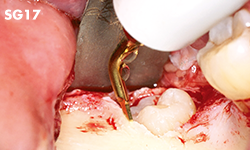

Escisiones en áreas con planos inclinados o proyecciones, o de difícil acceso con punta SG1 u otras puntas normales.

Corte de superficies curvas.

• POTENCIA [SURG] 80%

• Revestimiento de TiN

• Marca a 3 mm del filo de la punta

• Cinco dientes; 0,8 mm de grosor

Zonas de difícil acceso con puntas normales, especialmente zona mandibular posterior y zonas curvas.

Corte fino y preciso para reducir la pérdida ósea.Apta también para corticotomías.

• POTENCIA [SURG] 50%

• Revestimiento de TiN

• Extremo filoso

• 0,5 mm de grosor

Zonas de difícil acceso con puntas normales, especialmente zona mandibular posterior y zonas curvas.